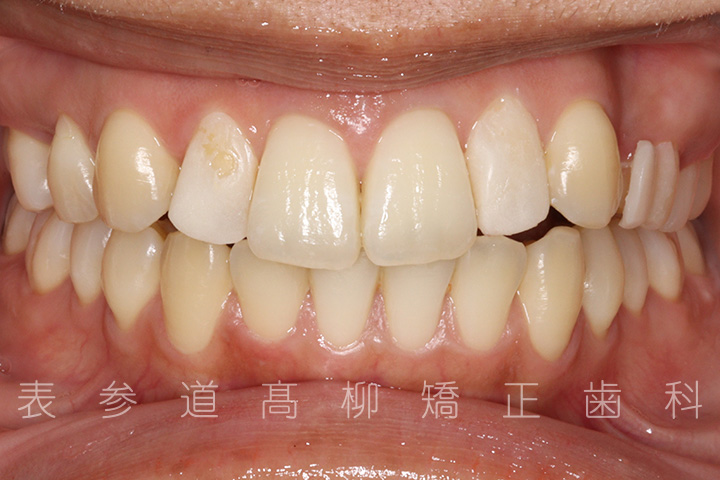

上の前歯が出ているのと前歯が小さいことをお悩みの患者様の症例をご紹介いたします。

・上顎前突(前歯の前方傾斜)

・2⏊2矮小歯(先天的に形態が小さい歯)

・上下前歯部叢生(凸凹歯並び)

術前術後の比較